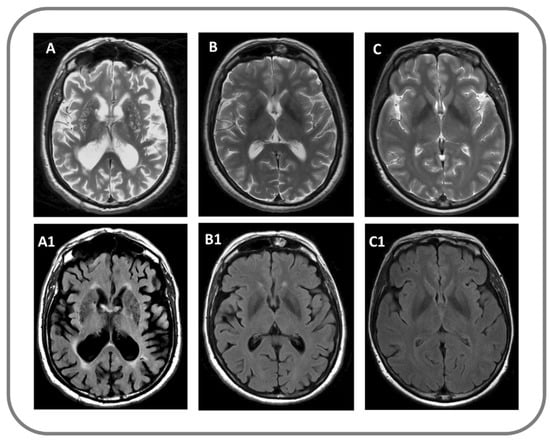

Demographic and clinical characteristics of participants are summarized in Table 1. Patients groups were not statistically different regarding onset, disease duration, and disease severity (Table 1). All PD patients (1/15, 100%) and six VP patients (5/13, 46%) had a good response to levodopa administration (p < 0.04). VP patients had a clinical subtype more frequently characterized by a combination of clinical symptoms, such as lower body progressive parkinsonism, poor levodopa responsiveness, postural instability and gait difficulties, rigidity and cognitive impairment. Significant differences were found in neuropsychological variables. More details are reported in Table 1. Status cribrosus of basal ganglia was present in VP but not in PD and controls on conventional MRI (Figure 2). Although DAT-SPECT uptake was markedly reduced in PD patients as compared to those with VP, no significant statistical differences emerged between these two groups (Table 1).

Figure 2.

Findings on conventional structural MRI in a patient with VP (A,A1), with PD (B,B1) and in a control subject (C,C1); (A–C) panels: T2-weighted image; (A1–C1) panels: Fluid attenuated inversion recovery (FLAIR) image.